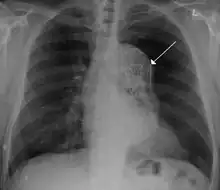

Blunt thoracic aortic injury

Advances in vascular surgery, specifically endovascular technologies, have led to a dramatic change in the operative approach to blunt thoracic aortic injury (BTAI). BTAI results from a high speed insult to the thorax such as a motor vehicle collision or a fall from a height. One widely-used classification scheme is based on the extent of injury to the anatomic layers of the aorta as seen with computed tomography angiography or intravascular ultrasound. Grade 1 BTAI are those which tear the aortic intima; grade 2 injuries refer to intramural hematoma; grade 3 injuries are pseudoaneurysm and are only contained by adventitial tissue; and grade 4 refer to free rupture of blood into the chest and surrounding tissue.[36] When indicated, first line intervention involves TEVAR.